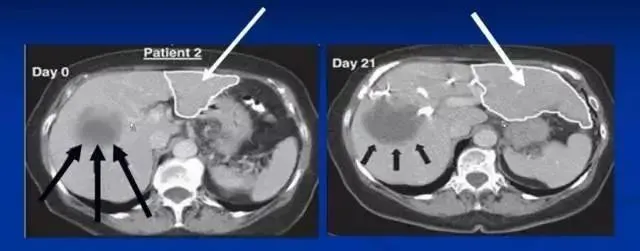

沈陽軍區總醫院消化內科郭曉鐘等經股動脈肝內自體骨髓干細胞移植治療肝硬化102例報告。

術后復查提示:

血漿蛋白改善在各項指標中最顯著,其次為凝血功能的改善,可改善肝臟合成蛋白功能,對目前肝硬化腹水的患者具有積極意義。

第2個明顯改善的指標為纖維蛋白原和凝血酶原時間,同樣代表肝臟的合成功能提高。